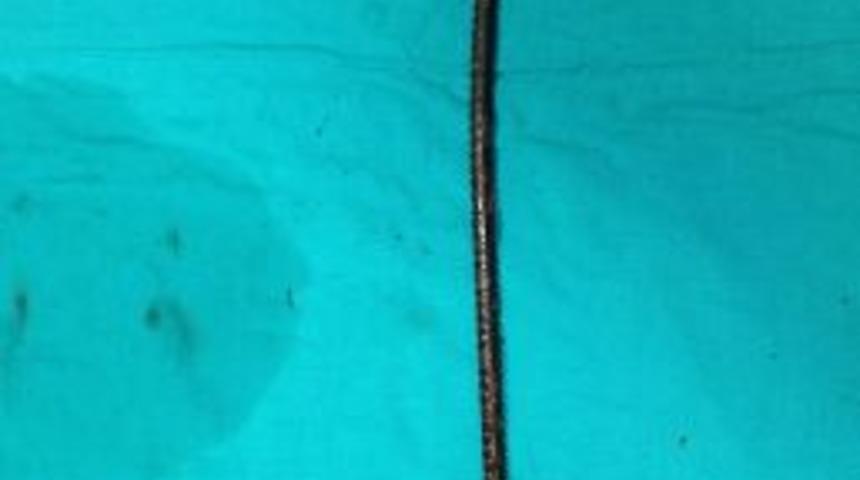

İnşaatın elektrik işlerinde çalışan 28 yaşındaki Serkan Kara, dengesini kaybedince üçüncü kattan kolon demirlerinin üzerine düştü. Demirlerden biri Kara’nın sağ kol altından girerek sol göğsüne kadar ilerledi. Kara olay yerine gelen itfaiye ekiplerinin çalışmaları sonucu düştüğü yerden çıkartılarak göğsündeki 35 santimetre uzunluğundaki demir ile Dr. Lütfi Kırdar Kartal Eğitim ve Araştırma Hastanesi’ne kaldırıldı.

Hastanede yapılan incelemelerde Kara’nın göğsündeki demirin sol kol altına kadar ilerlediği görülünce hemen ameliyata alındı. Sol akciğeri parçalayan ve kalp zarına zarar verdiği belirlenen inşaat demiri, cerrahların göğüs kafesinin her iki tarafında gerçekleştirdikleri eş zamanlı ameliyatın ardından çıkartıldı.

Kara’nın yanında basın mensuplarına konuyla ilgili bilgi veren Dr. Lütfi Kırdar Kartal Eğitim ve Araştırma Hastanesi Başhekimi Doç. Dr. Recep Demirhan akşam saatlerinde hastanın göğsünde inşaat demiri saplanmış olarak hastaneye getirildiğini söyledi. Demirhan şöyle konuştu: “Hastanın röntgenleri çekildi ve 35 santimetre uzunluğundaki demirin sağ göğüs altından girdiği, sağ ve sol akciğeri parçalayarak ilerlediği, kalp zarına hasar verdiği tespit edildi.” Eş zamanlı olarak sol ve sağ göğüsten yapılan çift taraflı ameliyat ile hastaya müdahale edildiğini, önce kalp zarının ardından iki akciğerin başarılı bir ameliyatla onarıldığını söyleyen Demirhan, saplanan demirin kalbe 3 milimetre daha yakından geçmesi durumunda Kara’nın yaşamasının mümkün olmayabileceğini sözlerine ekledi.